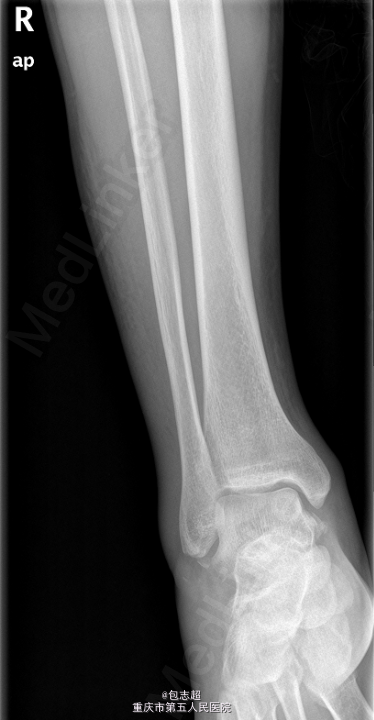

患者,男,31岁,因“外伤致右踝部胀痛活动受限10小时余”。 患者10小时发生车祸,右踝部被电瓶车压伤,外阴部撞伤,即感疼痛、肿胀伴活动障碍,无恶心呕吐,当地医院拍片示:右距骨骨折。

右踝部、右足背肿胀明显,局部青紫,无明显皮肤破裂出血,局部压痛明显,未及骨擦感,右踝关节活动受限,末梢血运尚可,感觉灵敏。外阴部可见缝合创口. 当地医院X线:右距骨骨折。

初步诊断:1、右距骨骨折2、会阴部撕裂伤;3.多处皮肤挫裂伤. 于全麻下行 右距骨骨折切复内固定术+三角韧带修补术. 沿内踝内侧做弧形10cm切口,逐层暴露,注意保护周围血管神经、肌腱,予内踝截骨,暴露距骨,见右距骨压缩性骨折,冲洗创面,清除血肿,手法复位骨块,确保跖跗关节对位好,克氏针临时固定,C臂机透视确认骨折脱位复位好。予5枚螺钉固定距骨骨折块。C臂机透视确认骨折复位及内固定位置良好。予2枚螺钉固定内踝,1枚铆钉固定三角韧带浅层。